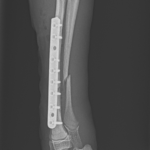

橈骨固定術 #241 Toy Poodleさん(7ヶ月齢)が室内で骨幹中央部からやや遠位の橈骨骨折をしたとの事。1.5コンベンショナルプレートで整復しました。しばらく安静が必要です。 症例カテゴリー 放射線治療整形外科軟部組織外科脳神経外科内科腫瘍外科救急・集中治療リハビリテーション科腫瘍内科内視鏡科脳神経科呼吸器外科中医・漢方猫の腎移植循環器科